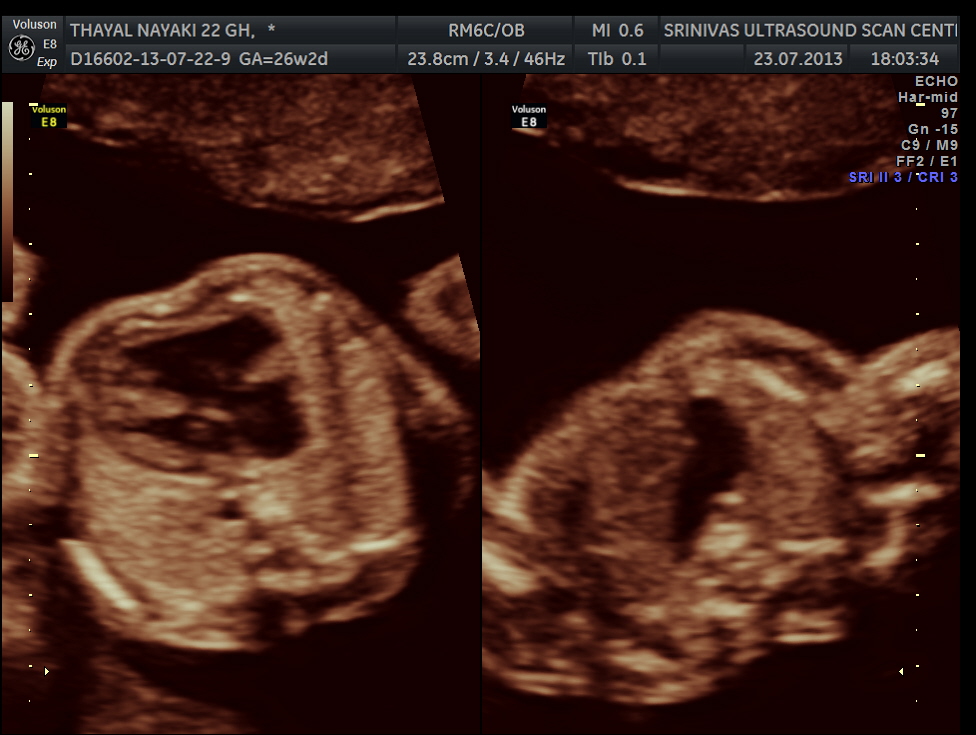

3 vessel view shows a prominent single vessel , which is very suggestive of outflow tract anomalies like transposition of great arteries, double outlet right ventricle , truncus arteriosus and corrected transposition of great arteries.

another view of the above two